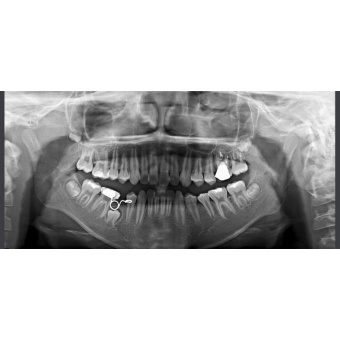

Rayscan a-SC (Alpha Pano Ceph) – панорамный рентгеновский аппарат последнего поколения с цефалостатом. Аппарат предназначен для панорамного сканирования зубов, челюстей и полости рта, а также включает в себя функцию сканирования для получения изображения головы. Специально разработанная конструкция аппарата позволяет в дальнейшем вне заводских условий произвести его дооснащение функцией компьютерной томографии (КТ). В стоимость аппарата входит мощный компьютер, программное обеспечение и беспроводной RF-пульт управления.

Высококачественное изображение

Ортопантомограф RAYSCAN является передовым диагностическим оборудованием, в котором применяются 2 сенсора: высококачественный плоский сенсор HAMAMATSU (Япония) для панорамной съёмки и отдельный сканирующий сенсор, которые обеспечивают чёткое изображение с первого раза (даже волос и мягких тканей), последний имеет различные режимы сканирования.

Каждый пациент имеет разную форму и размер челюсти, поэтому для получения качественных снимков необходимо учитывать эти индивидуальные особенности. При настройке аппарата предусмотрены 7 анатомических режимов, которые позволяют быстро ввести параметры съёмки с учётом индивидуальности пациента (размеры тела пациента: крупный, нормальный или худой; размер челюсти: взрослый пациент или ребёнок; проекции: височно-нижнечелюстные суставы (ВНЧС) или верхнечелюстные пазухи (Синус).

Программы съемки:

- Стандартная панорамная.

- Детская панорамная.

- Ортозональная панорамная.

- Панорамная съёмка широкой зубной дуги.

- Ортогональная проекция.

- Верхнечелюстные пазухи.

- Латеральная проекция (открытого, закрытого) височно-нижнечелюсного сустава (ВНЧС).

- 7 анатомических режимов.

- Телерентгенографическое (ТРГ) сканирование: 5 режимов

- размер изображения: 150 мм макс для панорамы, 260х225 мм для цефалометрии